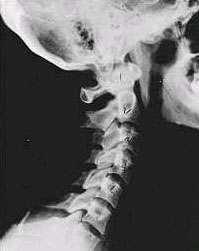

Normal

This is a picture of a normal spine. Compare this X-ray with the ones you will see below on this page. Notice the normal forward curve of the neck. This curvature helps absorb shock. Notice how each of the disc spaces between C2 (second bone in neck) and C7 are thick and even. Note that the front portions of each of the vertebrae are fairly open with clear and well defined borders (normal vertebrae in other parts of the spine have similar characteristics). If you have a subluxation in your spine that is left untreated, changes in the spine occur that result in damage to both the structure and function of the spine, and permanent nerve damage can result. |